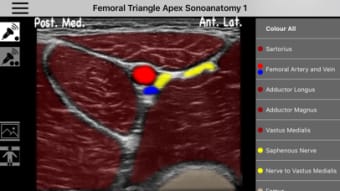

AnSo Anestesia Sonoanatomía es una aplicación para iPhone que proporciona una comprensión integral de la sonoanatomía relevante para el anestesista. Con más de 250 imágenes de ultrasonido y 1500 superposiciones de color de sonoanatomía, esta aplicación es un recurso conveniente diseñado para ayudar a los anestesistas a identificar la sonoanatomía común de manera eficiente en el tiempo dentro del ajetreado quirófano. Creado por anestesistas en ejercicio con interés en la enseñanza de la ecografía y la anestesia regional, AnSo proporciona múltiples ejemplos de la sonoanatomía ya que cada individuo es diferente.